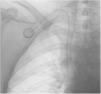

La sospecha de localización arterial la tuvo el equipo de enfermería de oncología cuando realizó la primera manipulación, 10 días después, con la salida de sangre arterial y pulsátil tras la punción de la cámara. Se confirmó la mala posición del dispositivo tras revisar la radiografía realizada después del procedimiento inicial, evidenciando la cámara situada en zona axilar, el trayecto del catéter con un bucle y el extremo distal en el cayado aórtico. (fig. 1). La exploración física de la paciente constató una única incisión y la ubicación axilar de la cámara.